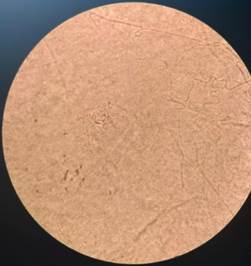

El servicio de parasitología realizó estudio micológico de la lesión sobre-elevada, verrucosa de surco nasogeniano izquierdo que reveló la presencia de las mismas levaduras en el examen directo (Figura 5) y en el cultivo (Figura 6).

Figura 5: Estudio micológico de la lesión de piel. A izquierda examen directo (en su fase filamentosa) y a derecha cultivos (en su fase levaduriforme). Fotos obtenidas por la Dra. Mariana González

Figura 6: Cultivo a 37ºC que muestra una colonia de aspecto cerebriforme que corresponde a la fase levadura del hongo.